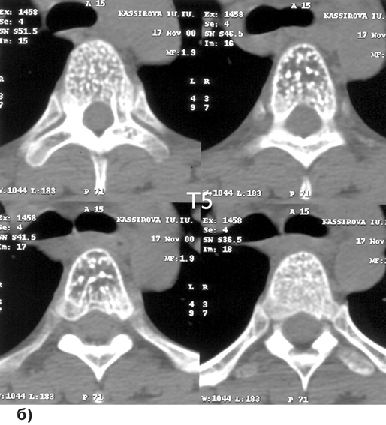

Морфологически выделяют капиллярные, кавернозные и смешанные формы, что не имеет существенного клинического значения. Выявляются обычно при МРТ как очаги повышенного сигнала как на Т1, так и на Т2-взвешенных изображениях (рис. 5а). Наибольшее диагностическое значение имеет КТ, при которой на аксиальных срезах обнаруживается зона перестройки костной ткани с четкими контурами, содержащая утолщенные трабекулы (“узор в горошек”) (рис. 5б).

; ;

Рисунок 5. Гемангиомы Th1–5–7:

а — МРТ, Т2-взвешенное изображение, сагиттальная проекция; б — КТ, аксиальные срезу через Th5 позвонок